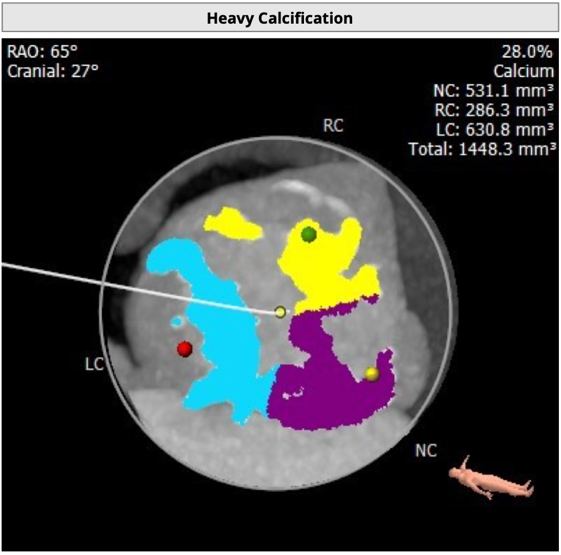

瓣叶严重粘连增厚,瓣叶钙化明显,HU850:1448.3mm³。

左冠开口高度8.6mm,右冠开口高度15.0mm,左冠高度偏低,左冠瓣瓣尖钙化明显,根据瓦氏窦内径和瓣叶长度综合判断,左冠存在较高堵塞风险;左心室后壁增厚。

1 患者为Type1型二叶式主动脉瓣,右无融合并形成钙化嵴,瓣叶极重度钙化伴严重增厚粘连;

2 患者左冠开口偏低,左冠瓣瓣尖钙化,结合瓦氏窦内结构,存在较大左冠堵塞危险;